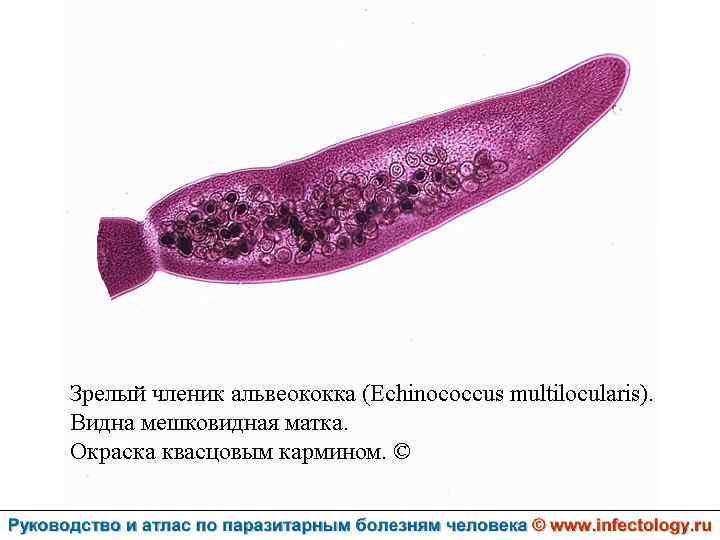

Альвеолярный (многокамерный) эхинококкоз человека (альвеолярный гидатидоз) (шифр по МКБ 10 - B 67. 5 -7) – зоонозный биогельминтоз, характеризующийся чрезвычайно тяжелым хроническим течением, первичным опухолевидным поражением печени, нередко с метастазами в головной мозг и легкие, а также во многие другие органы. Заболевание часто заканчивается летально.